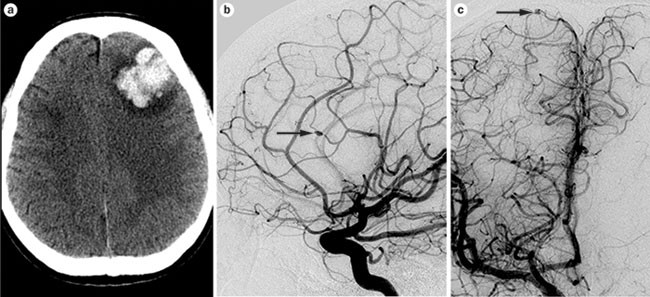

Intracranial Aneurysms From Vessel Wall Pathology To Therapeutic Approach Nature Reviews Neurology